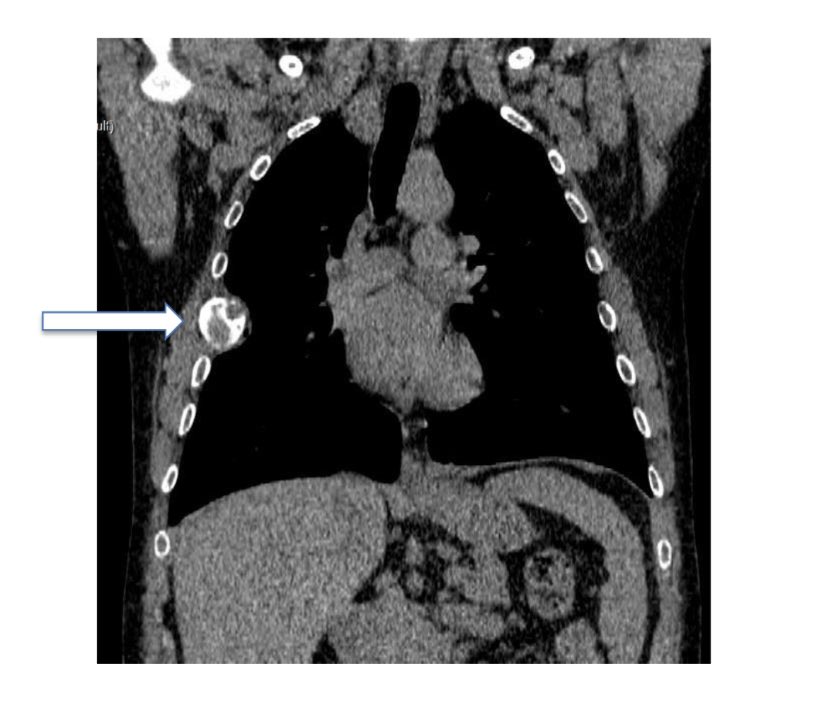

What would be your differential diagnosis and treatment strategy when you see these cystic/lytic lesions just pre-transplant? (PTH: 2411 pg/mL) You can check our team’s approach in the latest issue of Turkish Journal of Nephrology turkjnephrol.org/en/confu-tumor…